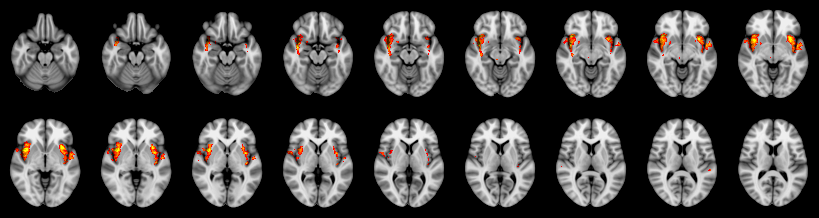

Pain study, Voxel-level, Corrected

Not combined

Face:

Hand:

Foot: